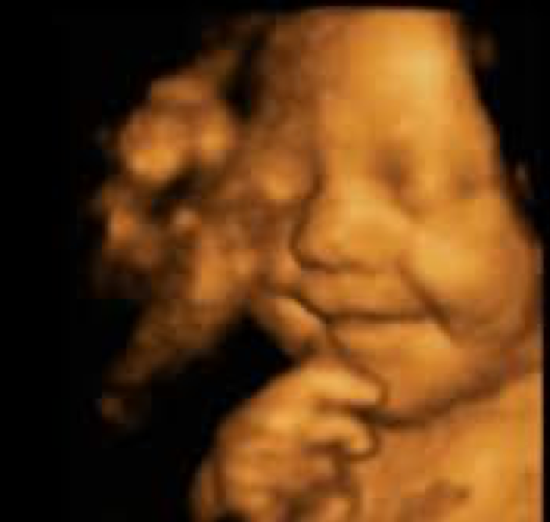

3D/4D Ultrasound

3D / 4D ultrasound presents a 3-dimensional picture in real-time Images are used to diagnose abnormalities both in Obstetrics and Gynaecology specific fetal anomalies such as limb abnormalities & cleft lip